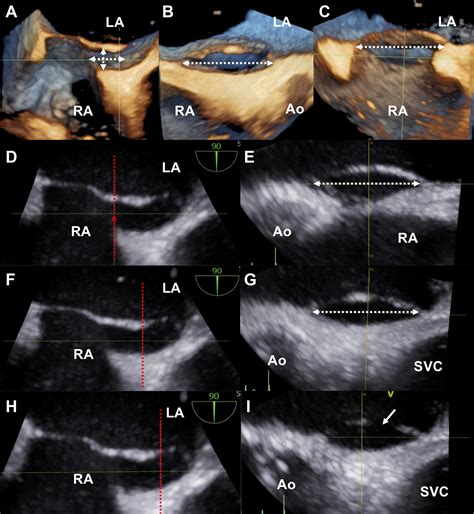

2408×2614

cvcasejournal.com

Three-dimensional Transesophageal Echocardio…